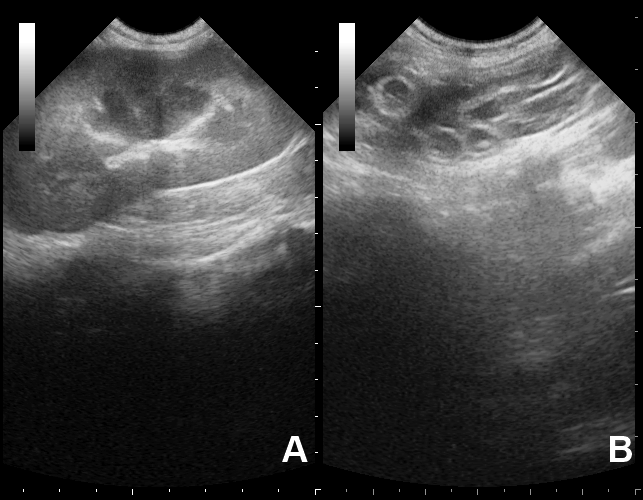

Podemos caracterizá-lo como uma estrutura tubular, de dupla parede hiperecóica e de aspecto flexível. Seu diâmetro é variável mas quando adulto mede em torno de 1,0cm. O comprimento geralmente não é mensurável devido a apresentar-se enovelado (enrolado). Quando parasia o rim, tende a destruir todo o parênquima e ficar flutuante no líquido intracapsular.

Em todas as localizações, as características ultrassonográficas são semelhantes.

Em topografia de rim direito observa-se estrutura tubular, de dupla parede hiperecóica, medindo 1,0cm de diâmetro, aspecto flexível e com distribuição enovelada, envolta por material anecóico circundado pela capsula hiperecóica (cápsula renal) - imagens compatíveis com parasitismo renal direito por Dioctophyma renale.